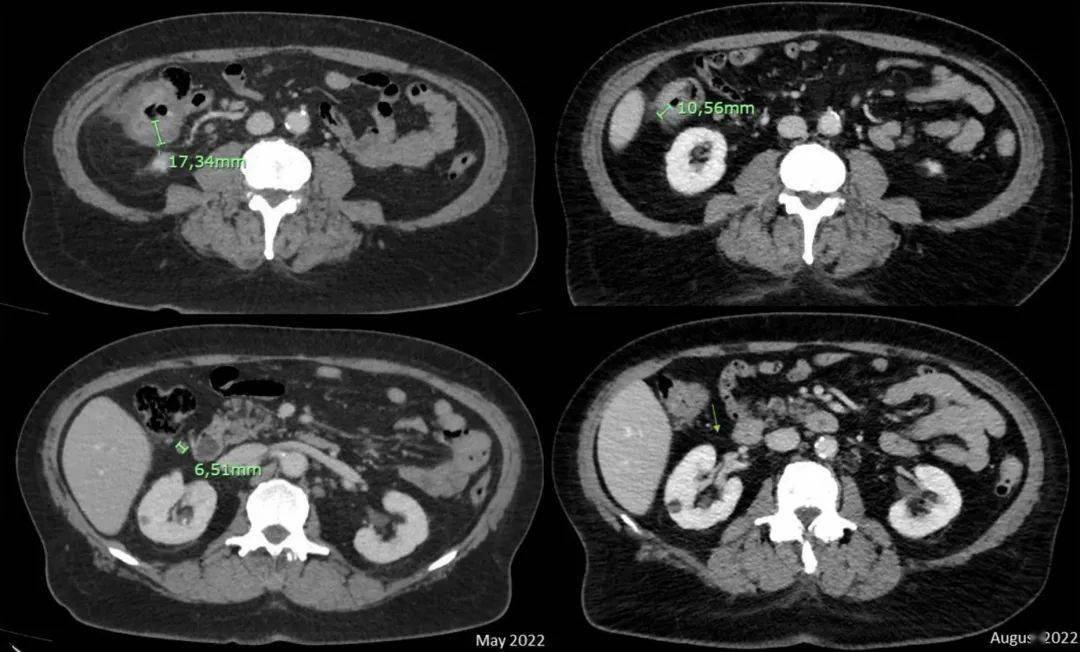

岂有此例丨dfs超过5年首个单中心转移性晚期结直肠癌系列病例分享

新辅助免疫治疗在 dmmr/msi-h 结直肠癌转化治疗中的疗效如何?